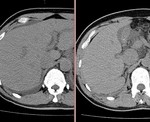

[画像診断]AFP産生胃癌について 2010-09-14